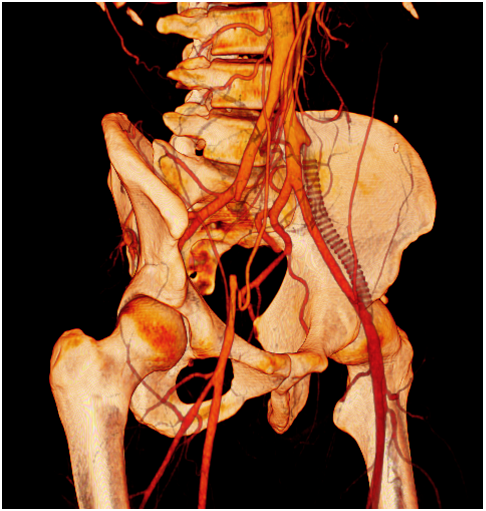

One year later he was visited for the appearance of ischemic symptoms in the right lower limb, calf claudication, pulselessness and subtle pallor, with no critical ischemia signs. An emergency duplex ultrasound evaluation showed a pathological Doppler curve and lowered systolic blood flow speed in the right femoral artery thus suggesting iliac stenosis. With the diagnostic orientation of a complicated right EIA endofibrosis, low molecular weight heparin was prescribed to avoid progressive thrombosis and a new angio CT scan was performed. The CT scan demonstrated an acute thrombosis of the right EIA, with patency of the previously revascularized left EIA, and an endovascular revascularization was programmed (Figure 1) (Figure 2).

Figure 2 CT scan oblique reconstruction showing occlusion of the right EIA, the occluded iliac prosthetic graft and patency of the native left iliac arteries after revascularization.

Iliac artery endofibrosis is a challenging pathology because it affects very young people with possible devastating effects but aetiology and therapeutic options remain uncertain. Even though literature raises the idea that open surgical repair is the most definitive option, we consider treatment indication should be individualised in all patients. In this case there are three factors that made our department decide to apply endovascular procedures. The first reason was the existence of a failed prior open surgery. When revising the angioCT scan and angiography images, we identified an important psoas and lumbar muscular hypertrophy that seemed to be the external mechanical reason of the bypass graft obliteration due to an external compression. Furthermore, in angiographic images no significant psoas artery collaterals were observed, thus suggesting that there was no EIA tethering to be solved, and iliac artery elongation was not notorious. It therefore seemed that there were no significant anatomical factors that would benefit from open surgical correction. Instead, in such a young and active patient open surgery carried higher complication rates and longer recovery periods after surgery. Endovascular options are technically feasible, with low and minor complication rates when compared to open iliac revascularizations, and even though these seem to have a limited patency in time, this case shows that endovascular iliac revascularizations are easily reproducible with optimal immediate results and minimal hospital admittance. Nevertheless, either endovascular or surgical procedures fail if the mechanic origin of the iliac artery endofibrosis persists. Our patient underwent intensive clinical controls and a correct medical treatment to enhance endovascular revascularization patency and to prevent thrombotic events, but there was no sport cessation. According to clinical history, acute symptoms usually appeared after competitions of intensive trainings. It seems that this patient had bilateral EIA endofibrosis due to triathlon competitions and training (including intensive cycling sessions), probably due to the external continuous mechanic trauma of hypertrophic lumbar muscles adjacent to the IAE (Figure 5). In this context, some especially intensive efforts involving important dehydration may have led to complication of the endofibrotic area causing the EIA spasm and thrombosis.